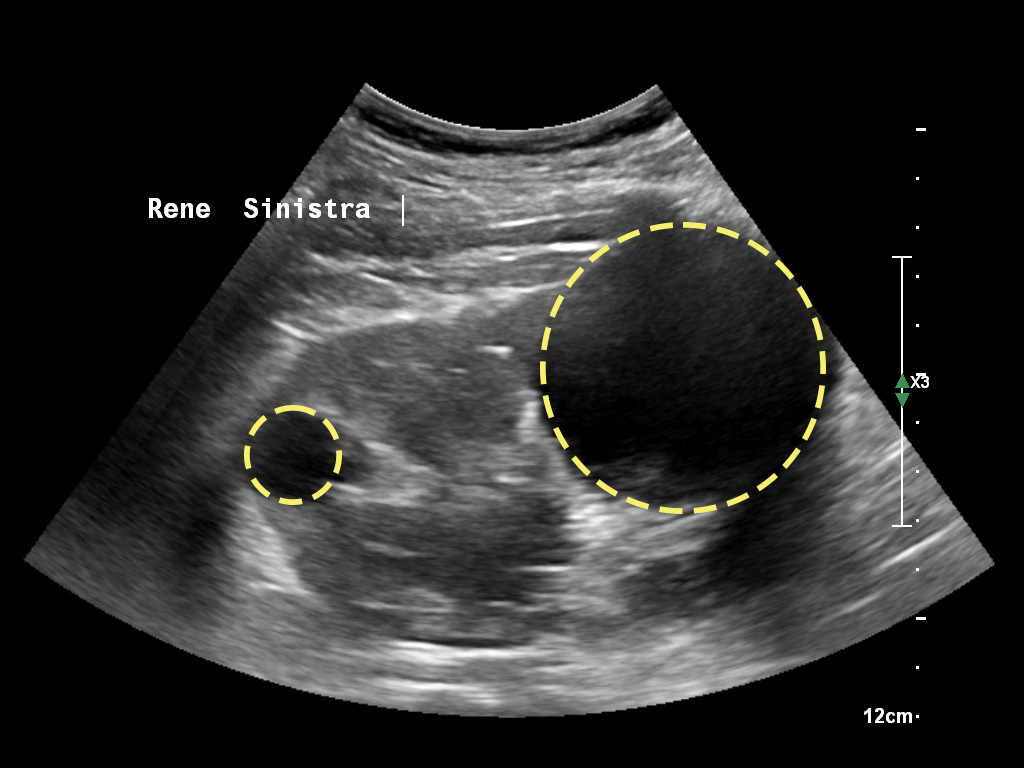

Cisti Renali

Una cisti è una sacca, generalmente ripiena di liquido, delimitata da una parete che separa il contenuto da ciò che circonda la cisti stessa. La cisti renale semplice di per sé è una lesione benigna. A volte possono essere associate a disturbi potenzialmente dannosi per la funzione renale o per l’organismo. Le cisti del rene possono essere lasciate in sede senza…